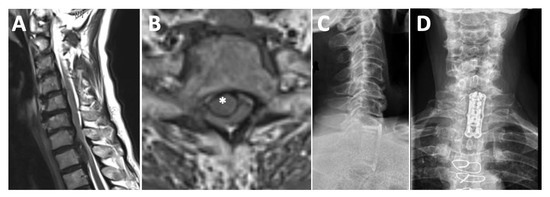

3.5. Case Illustration 2: Junctional Disc Herniation

A 74-year-old female patient presented with a 2-month history of progressive spinal ataxia of the lower extremities, midback pain, and myelopathic signs with decreased sensation distributed below T2. After lifting a heavy weight, symptoms deteriorated. MRI revealed a C7/T1 central disc herniation with severe spinal cord compression and acute myelopathy (Figure 2A,B). The CT showed extended calcifications of the herniated disc sub-totally occupying the spinal canal. The patient was treated via an anterior approach with partial sternotomy, C7 and T1 corpectomy, and microsurgical decompression of the spinal canal. Vertebra replacement was achieved with an expandable cage and anterior plating in a standalone concept. Postoperatively, the patient experienced immediate relief of her myelopathic symptoms and was able to walk without assistance by postoperative day 7. At 3 months follow-up, the patient reported complete symptom relief with no residual back pain. Figure 3 shows the preoperative MRI and the postoperative X-ray.

Figure 3.

Junctional disc herniation. Preoperative T2-weighted MRI in sagittal (A) and axial (B) orientation showing a large C7/T1 central disc herniation with caudal extension to T2, severe spinal cord compression, and acute myelopathy (herniated disk is highlighted by * in (B)). Postoperative X-ray in lateral (C) and anterior-posterior (D) view, confirming excellent implant position after standalone anterior treatment.